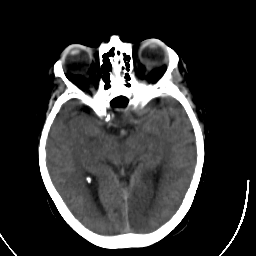

Stroke CT #3 -- Slice #10

[Home][Help][Clinical] Slice 10